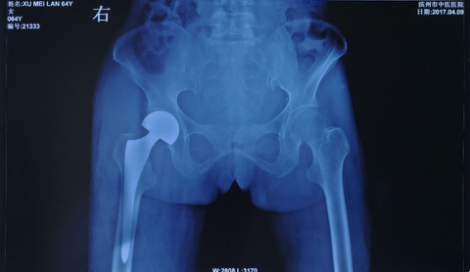

术后X线片

手术在腰硬联合麻醉下进行,手术通过切断股骨头圆韧带,取出股骨头,后置入人工股骨头假体,保障患者股骨头松紧度和活动度良好。术后患者配合中医康复治疗,病情恢复情况良好,可下床进行适度活动。